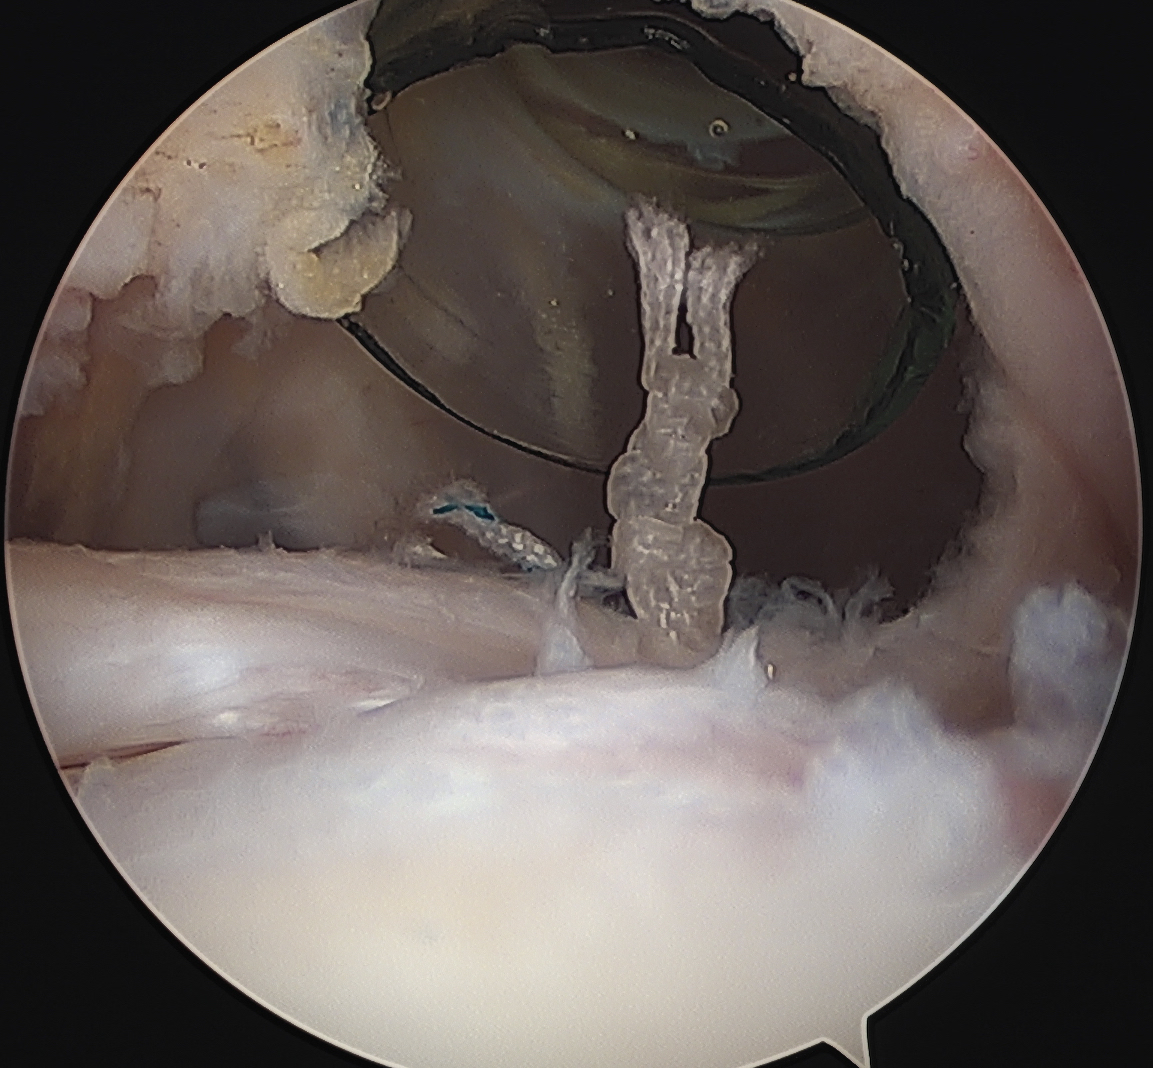

Technique

Subscapularis repair

Biceps pulley repair (coracohumeral ligament) +/- reconstruction +/- bicipital groove deepening

Bennett et al Arthroscopy 2004

- 12 cases of medial biceps subluxation

- treated with subscapularis repair and lateral repair of coracohumeral ligament over biceps

- one patient required later tenodesis

McClelland et al Acta Orthop Belg

- 16 cases of medial biceps subluxation

- treated with subscapularis repair / biceps pulley reconstruction +/- groove deepening

- at later ultrasound, 50% demonstrated LHB was tenodesed